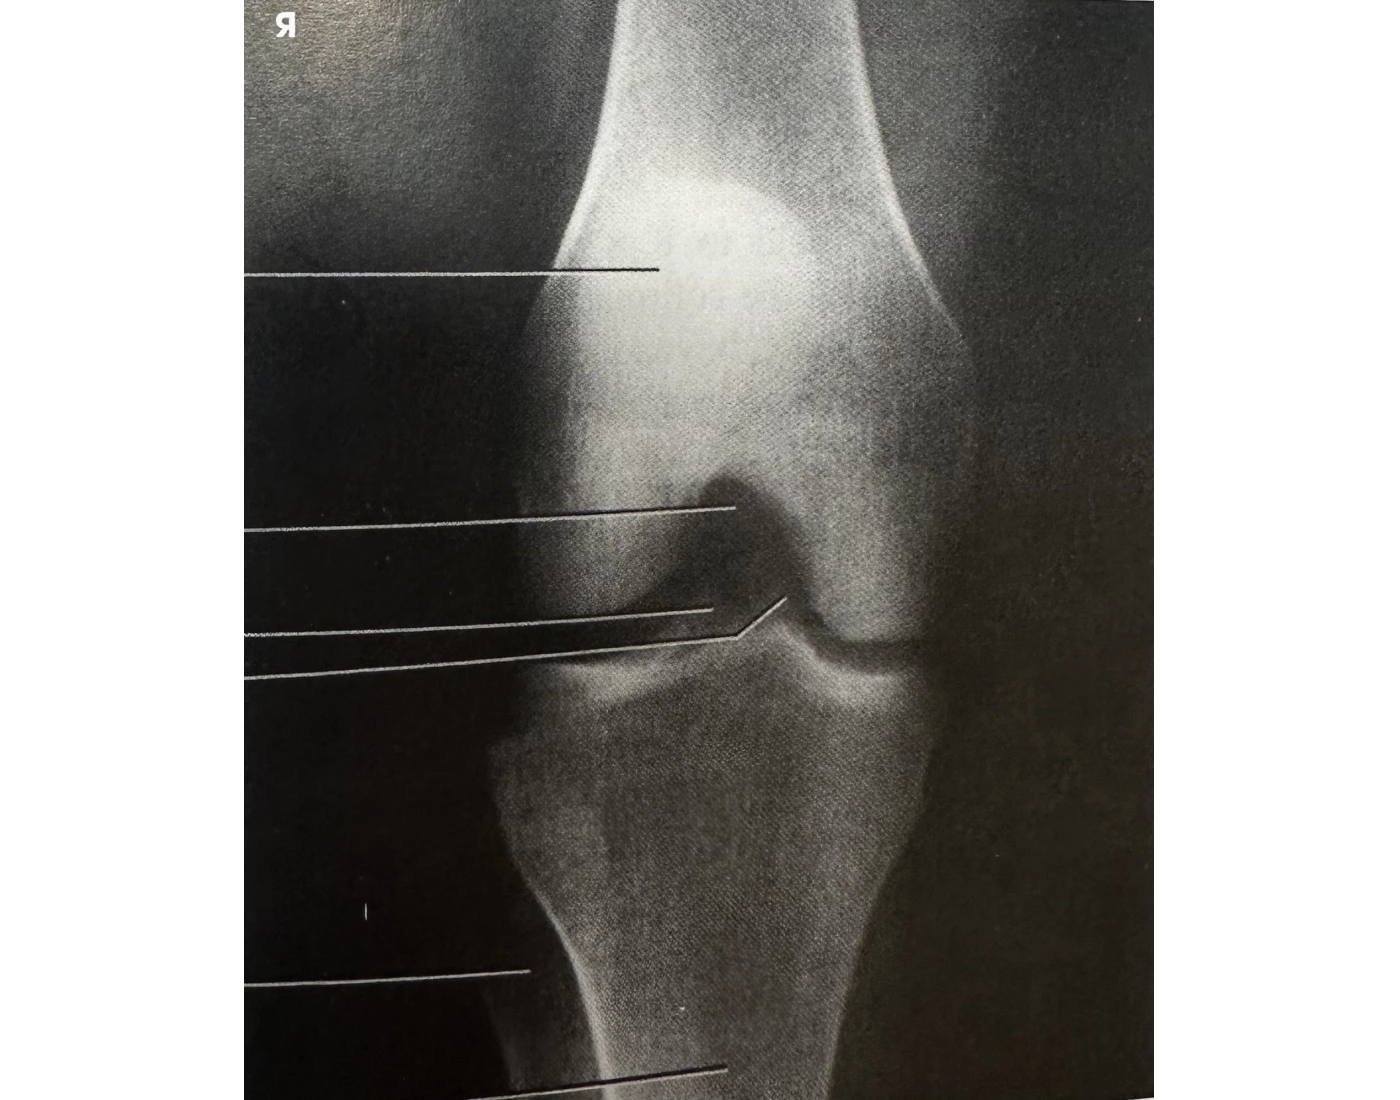

if patient’s asis is between____ and______cm high, you can shoot an AP knee with no angle

What angle for fat asses?

19-24

5° cephy